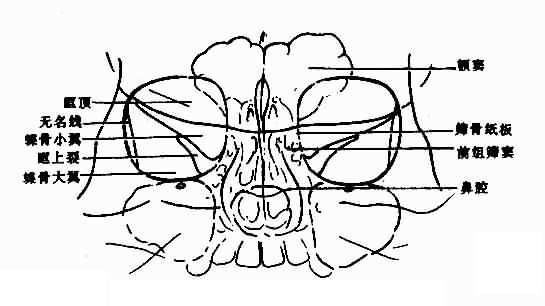

眼眶平片应观察:眶窝大小与形状,眶壁,包括眶顶、蝶骨小翼、蝶骨大翼、眶上裂、筛骨纸板(图5-2-1)等和眶窝密度,上述表现在两侧眼眶基本对称。

图5-2-1 正常眼眶(200后前位)